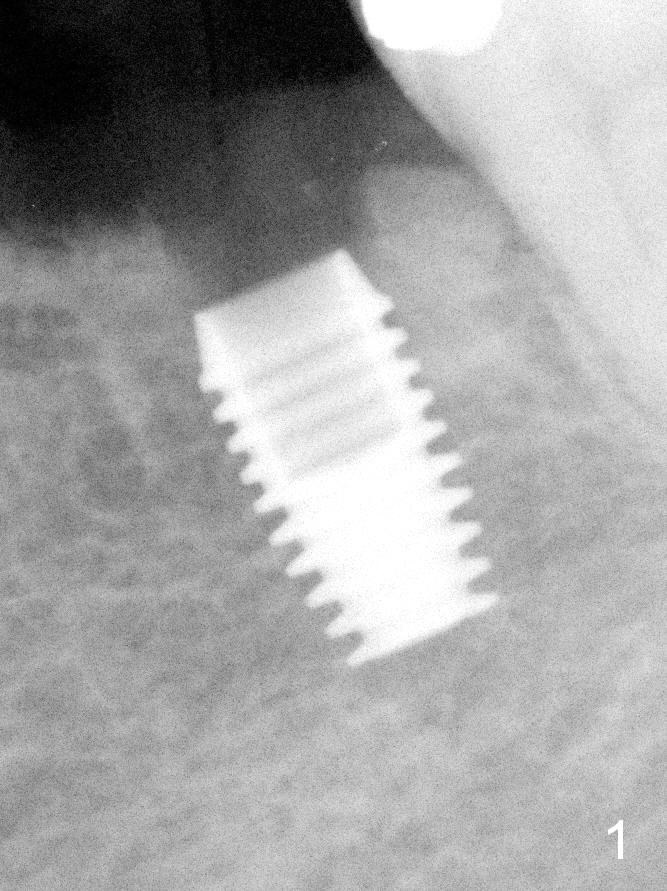

All of the 5 implants shown above are ~ 5 mm in diameter, placed in the lower 1st molar site. The first implant system used in my office is press fit (Fig.1). The reason to switch is its inability for immediate implant. The tissue-level implant appears to have aggressive thread patterns (Fig.2, bone/Titanium ratio: 50/50). To improve cosmetics, a bone-level implant is used (Fig.3). To enhance primary stability, a better thread patterned implant is chosen (Fig.4, bone/Titanium ratio: 70/30). It is apparent that IBS implant has the sharpest threads (fins, bone/Titanium ratio: 90/10, Fig.5)). It is consistent with my clinical cases. All of the implants mentioned above are placed at the site of #19 with diameter 4.5-6 mm and length 8-17 mm.